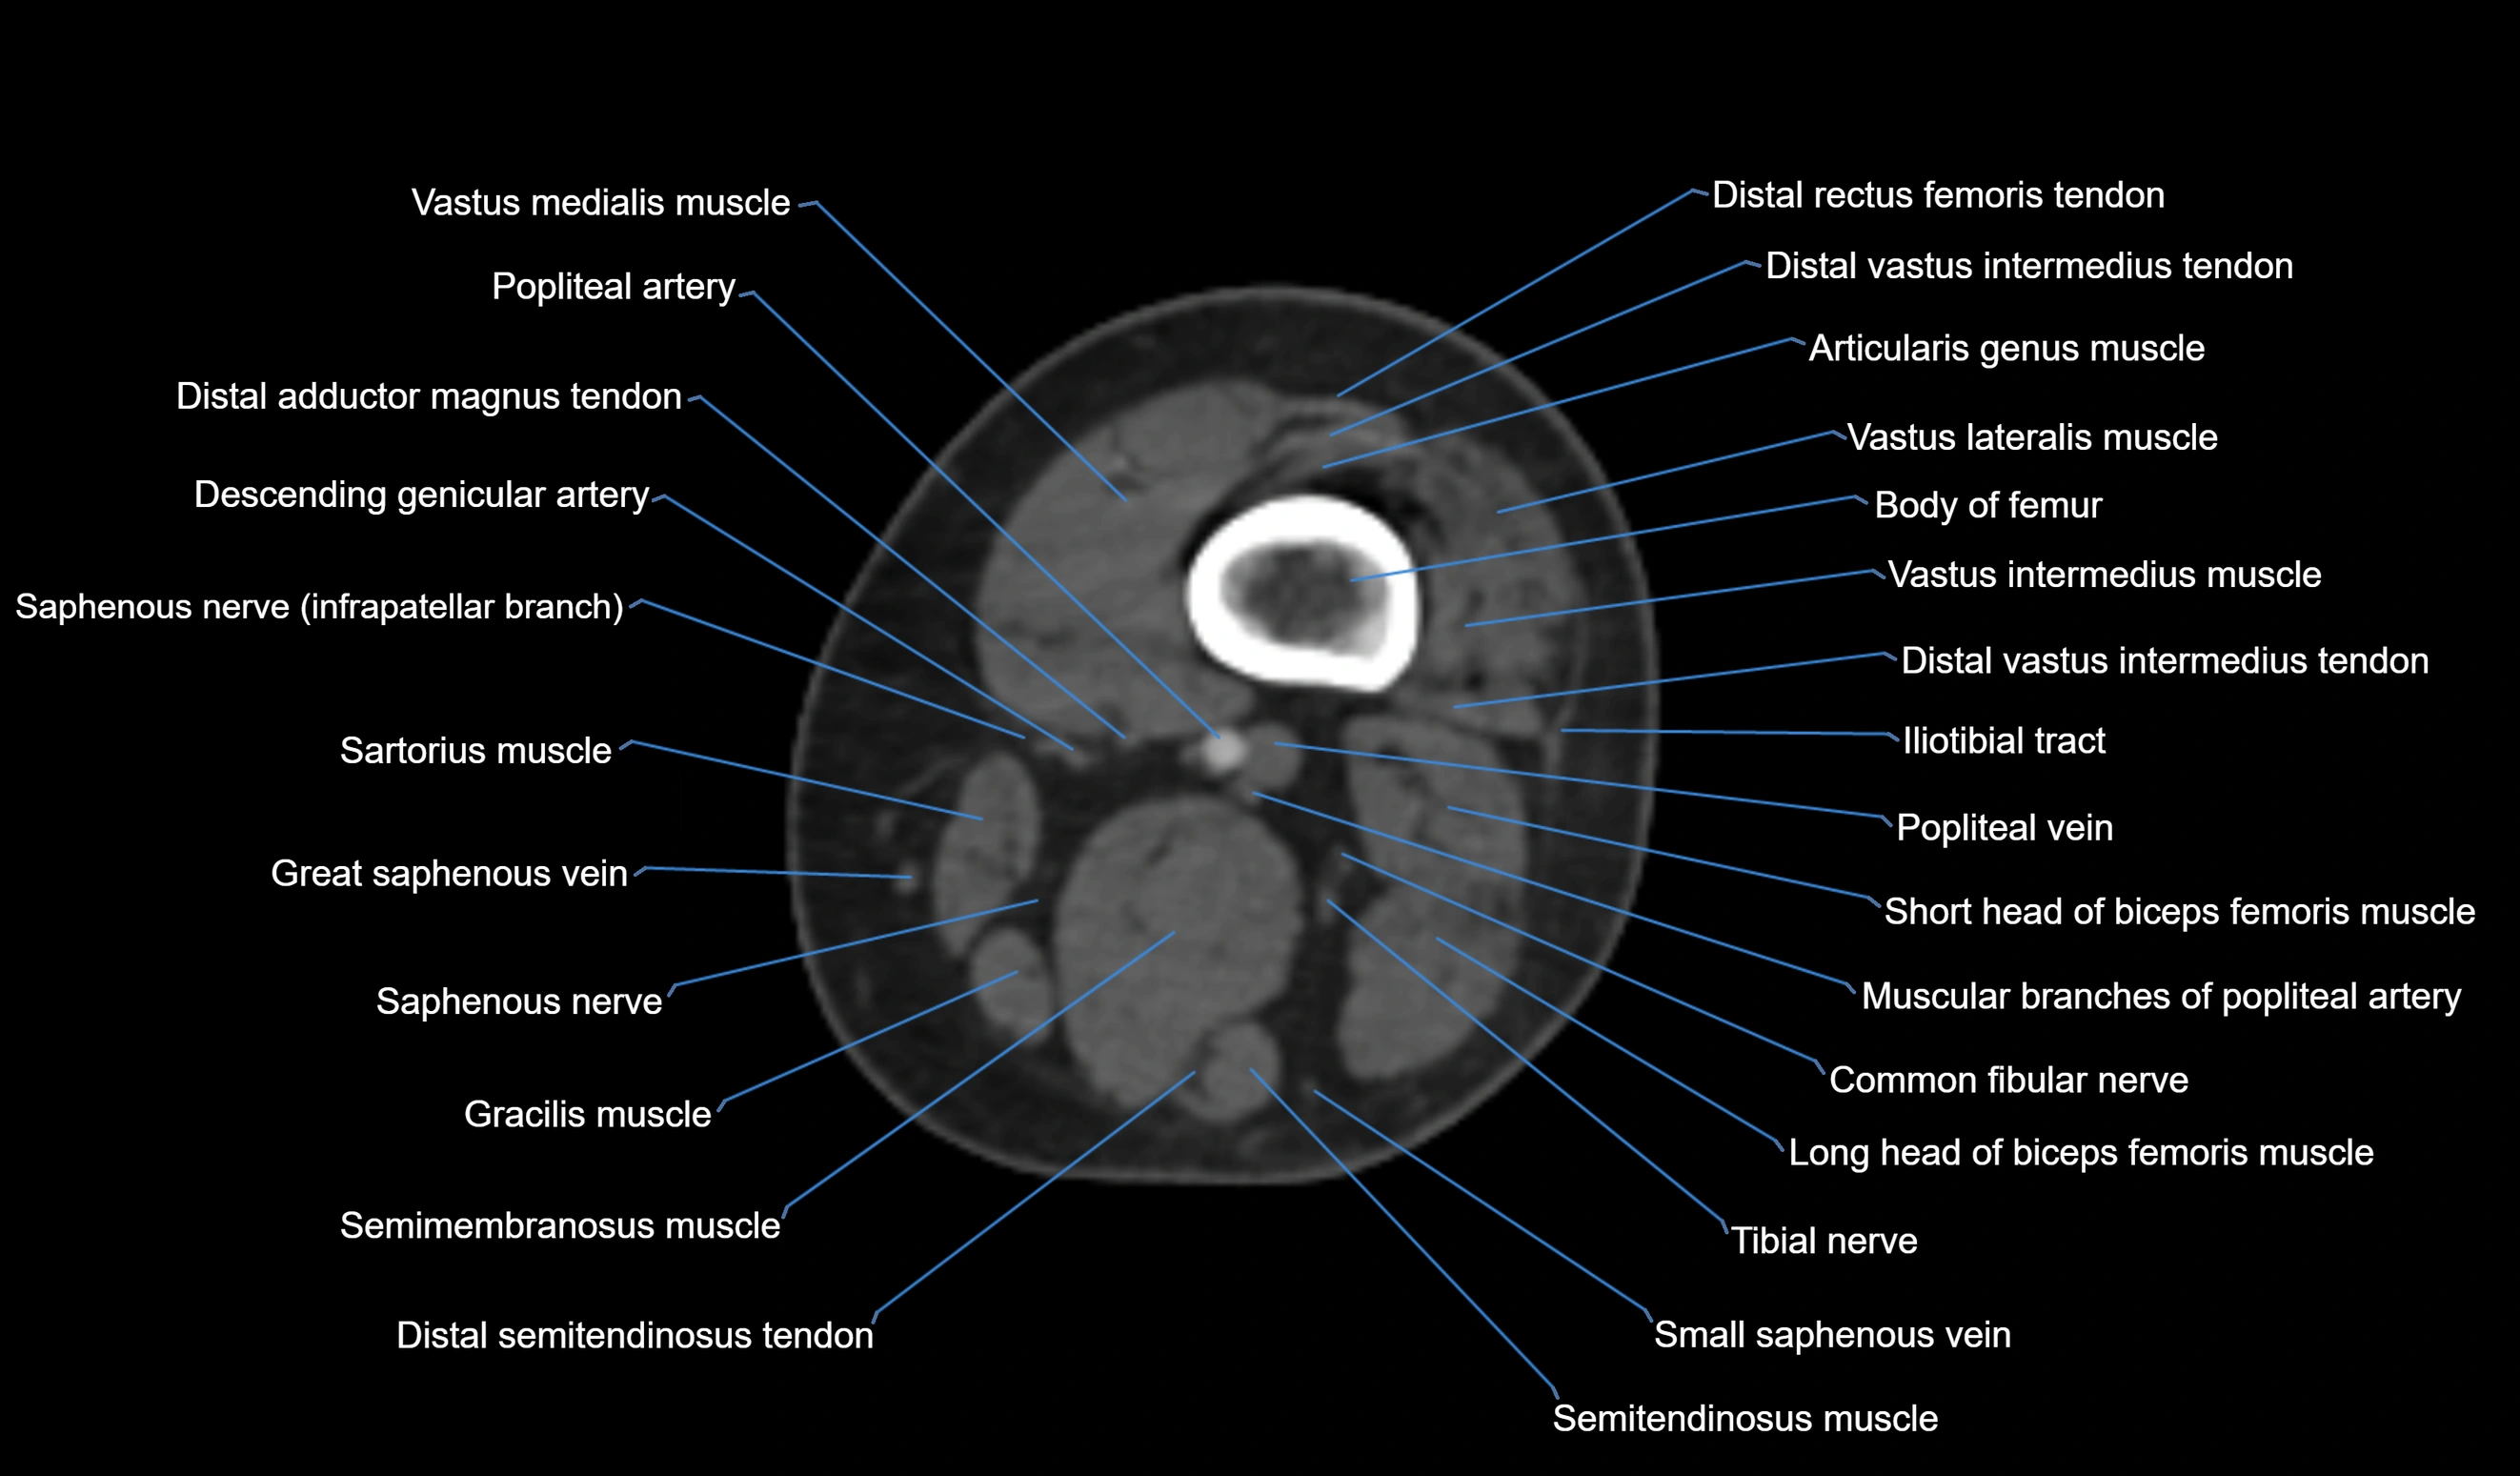

- Body of femur

- Distal adductor magnus tendon

- Distal rectus femoris tendon

- Distal vastus intermedius tendon

- Distal vastus lateralis tendon

- Popliteal artery

- Popliteal vein

- Sartorius muscle

- Semimembranosus muscle

- Semitendinosus muscle

- Small saphenous vein

- Tibial nerve

- Vastus lateralis muscle

- Vastus medialis muscle